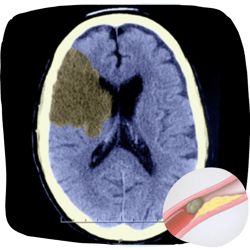

Hemorrhagic Stroke

Deadly Brain Bleeds

Though less common, hemorrhagic strokes are far more likely to be fatal. They strike when a weakened blood vessel bursts, causing uncontrolled bleeding in or around the brain. Aneurysms and AVMs (arteriovenous malformations) are structural weaknesses that make this type of stroke possible.